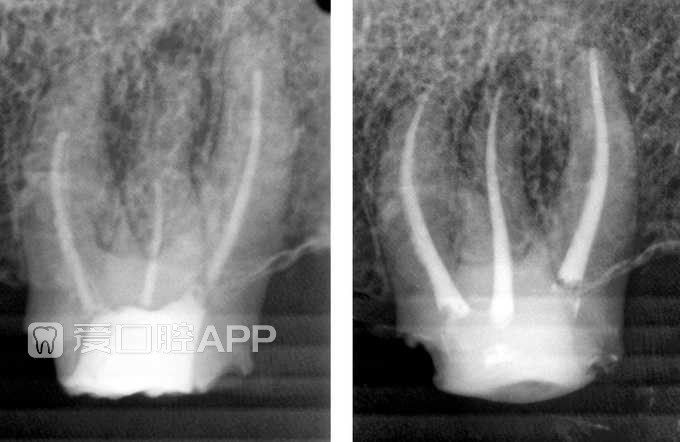

左上第三磨牙的再根充 by Tarek Cheriet